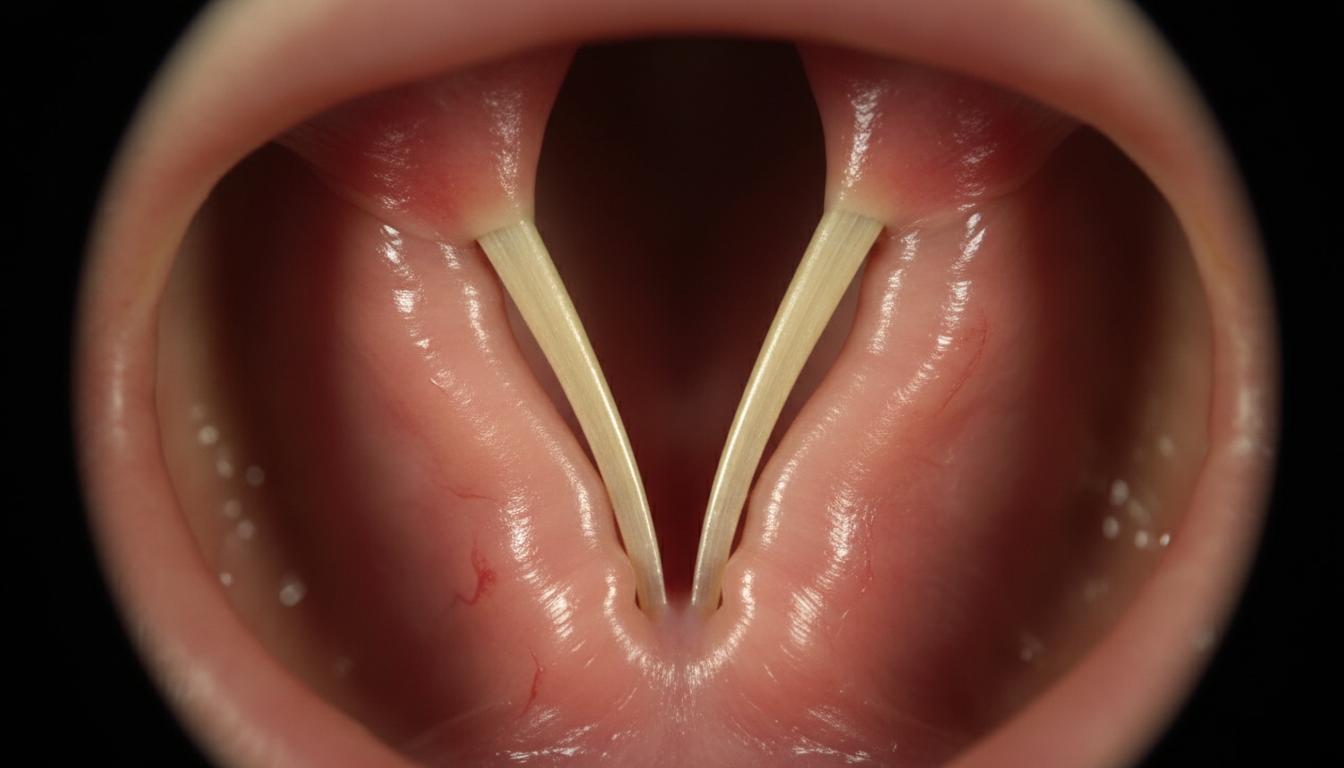

Struny głosowe – a właściwie fałdy głosowe – to dwie elastyczne struktury zlokalizowane w krtani, których ruchu nie doceniamy… dopóki ich nie tracimy. Za każdym razem, gdy oddychasz, mówisz, śmiejesz się lub połykasz, twoje struny pracują jak wyspecjalizowane zawory – otwierając się i zamykając w milisekundowych odstępach. Ich unerwienie pochodzi głównie z dwóch nerwów: błędnego (nervus vagus) oraz nawracającego (nervus laryngeus recurrens). To one sterują najdrobniejszymi skurczami mięśni krtani, dając ci swobodę wyrażania siebie, a jednocześnie chroniąc przed zachłyśnięciem.

Struny głosowe – bez nich nie tylko nie mówisz, ale także tracisz ochronę dróg oddechowych.

Parzyste struktury w krtani zbudowane z mięśni i więzadeł, których napięcie i pozycja decydują o emisji dźwięku oraz ochronie dróg oddechowych przed aspiracją.